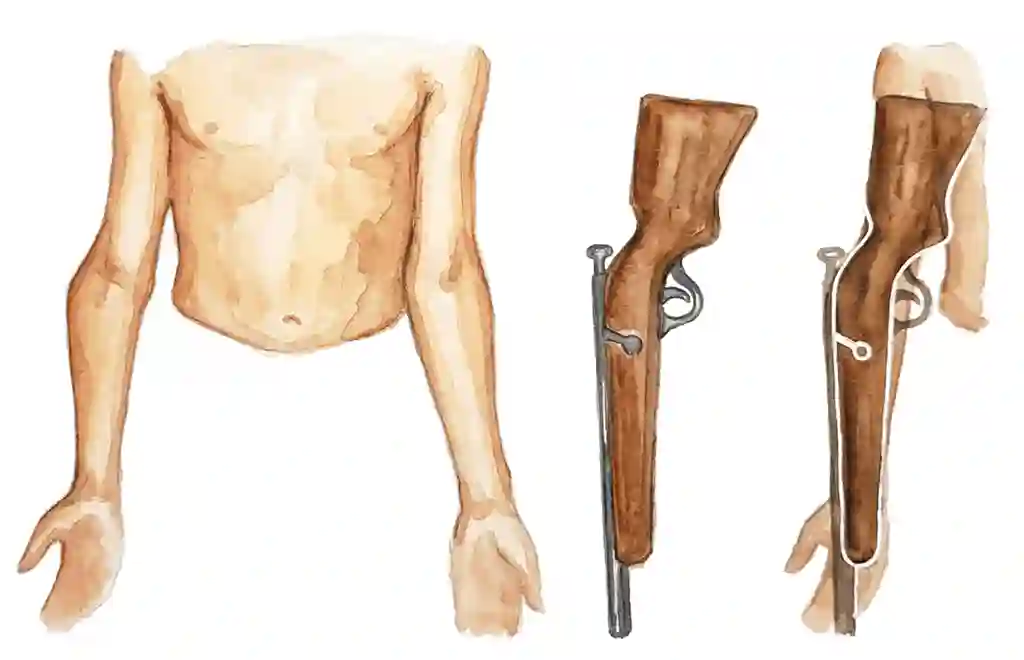

Cubitus Varus - Gunstock Deformity

Cubitus Varus (क्यूबिटस वेरस) एक elbow deformity है जहाँ arm बाहर की ओर bow (मुड़ना) बना देता है। इसे "Gunstock Deformity" भी कहते हैं क्योंकि arm पुरानी बंदूक के stock जैसा दिखता है।

Cubitus Varus, also called "Gunstock Deformity", is an elbow deformity where the arm bends outward creating a bow or crooked appearance - resembling an old rifle's gunstock.

इसे "Gunstock Deformity" भी कहते हैं क्योंकि arm पुरानी बंदूक के stock जैसा दिखने लगता है।

Cubitus Varus is an elbow deformity where the child's arm bends outward creating a bow-like appearance.

It is also called "Gunstock Deformity" because the arm resembles the stock of an old rifle.